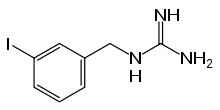

| Formula | C8H10IN3 |

| Molar mass | 275.093 g·mol−1 |

Iobenguane, or MIBG, is an aralkylguanidine analog of the adrenergic neurotransmitter norepinephrine (noradrenaline), typically used as a radiopharmaceutical.[3] It acts as a blocking agent for adrenergic neurons. When radiolabeled, it can be used in nuclear medicinal diagnostic and therapy techniques as well as in neuroendocrine chemotherapy treatments.